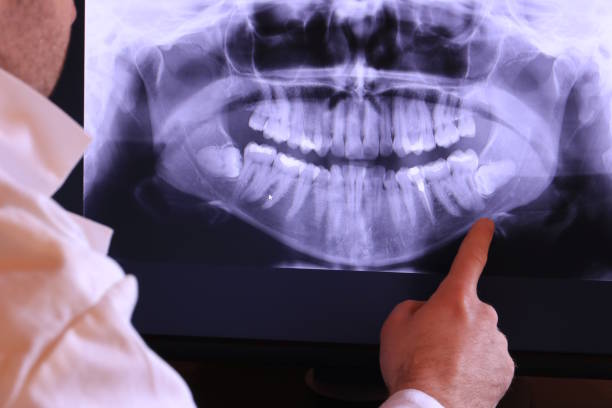

Urgent Dental Care for Toothaches in Murrells Inlet, SC

Experiencing severe tooth pain Our urgent dental care services are available to address your toothache with expert care and speedy solutions. Call us for immediate help!